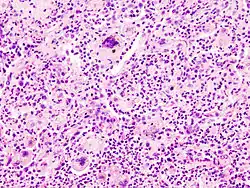

- TOUTON-Riesenzelle - Schaumzellen, bei denen um eine kleine schaumfreie Insel mehrere Kerne ringförmig angeordnet sind, Vorkommen z.B. bei juveniler Xanthogranulomatose, siehe Abb.

![]() |